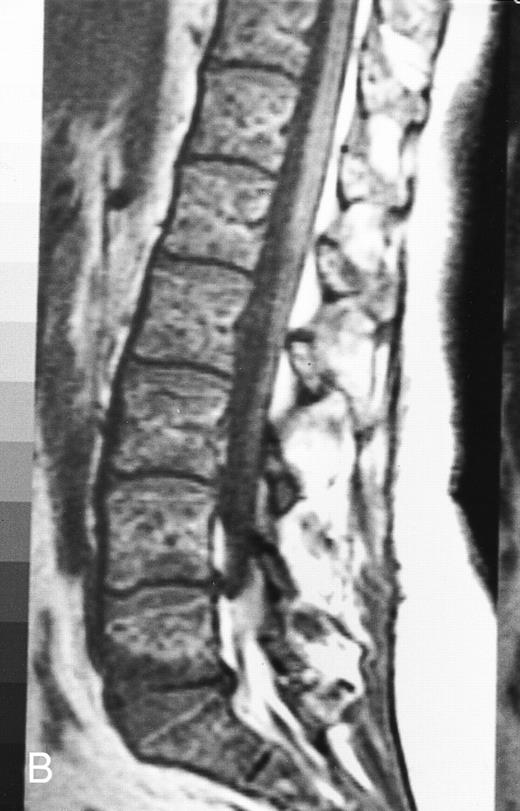

T1-weighted (500/11, TR/TE) sagittal MR images of the lumbosacral spine in a 45-year-old woman before (A) and 40 days after (B) bone marrow transplantation for multiple myeloma. There is a diffuse MR pattern of marrow involvement in (A) (bone marrow plasma cells, 50%; monoclonal protein, 6.0 g/dL). On the posttreatment image, there is definite reinstitution of fatty marrow in the spine and, in particular, around the basivertebral veins, in keeping with partial response to treatment (bone marrow plasma cells, 0.5%; monoclonal protein, 1.6 g/dL).